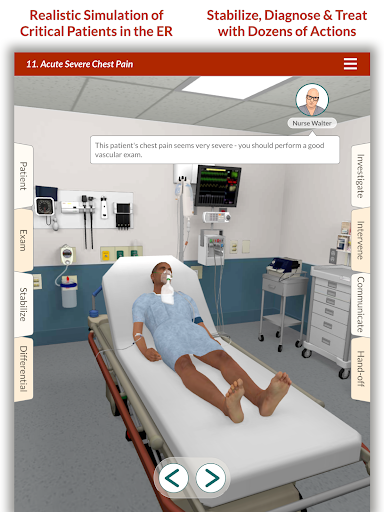

Đào tạo mô phỏng theo yêu cầu của Full Code với các bệnh nhân ảo thực tế cho phép bạn thực hành các trường hợp phức tạp và nâng cao kỹ năng của mình bất cứ khi nào bạn có thời gian nghỉ ngơi, bất kể bạn ở đâu, trên các thiết bị bạn đã sở hữu. CẢI THIỆN SỰ TỰ TIN

Các trường hợp có thể lặp lại vô hạn của Full Code đo lường các kỹ năng trong cả chẩn đoán và quản lý, cho phép bạn học hỏi từ những sai lầm của mình trong một môi trường không có rủi ro. Xây dựng năng lực để bạn có thể đối mặt với các trường hợp thực tế phức tạp một cách tự tin.

Mỗi trường hợp đều là một thách thức mới trong Full Code: từ chẩn đoán thông thường đến các bệnh hiếm gặp. Bạn không chỉ giới hạn ở bệnh viện—Full Code đã mở rộng sang nội dung trước khi nhập viện và EMS. Ra khỏi khoa cấp cứu và vào xe cứu thương để ứng phó với mọi tình huống mới!

— Cải thiện Âm thanh & Hình ảnh —

Bệnh nhân và cảnh của chúng tôi trông và âm thanh chân thực hơn bao giờ hết.